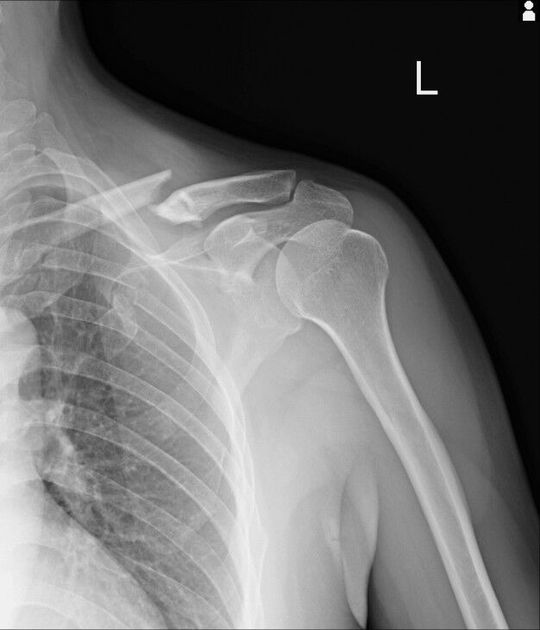

Clavicle

Fracture of left clavicle